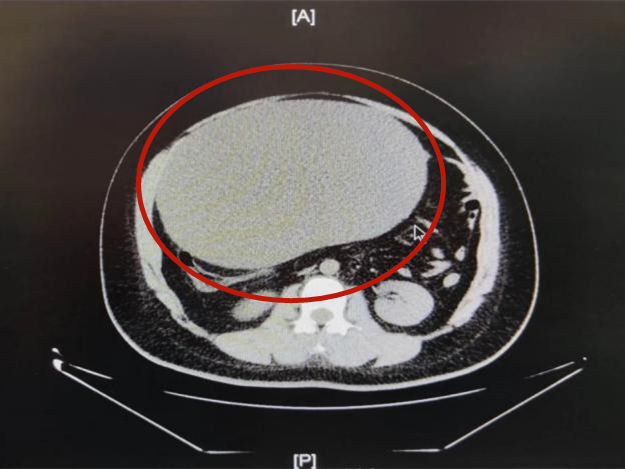

北院区急诊科东谈主员马上将晓琪转运至郑州东谈主民病院院总部,进行CT查验后表示: 晓琪的腹部盆腔内有一个庞大的囊性病变,这个囊肿压迫着周围的肠管与左侧子宫附件

通过超声查验再三证据后晓琪患上的是卵巢囊肿。况兼这个囊肿已经发生了扭转,淌若治疗不足时很可能导致该侧卵巢坏死。晓琪被坐窝送往妇科进行急诊手术治疗,妇科张喜红主任等为她履行了卵巢囊肿剔除术。

因囊肿庞大,小切口后经负压诱导器抽洗囊液,并快速病理查验。术后晓琪病情结识,生命体征安靖。

术后经野心,晓琪切除的卵巢囊肿重达16斤十分于“三胞胎”同样的分量。 简直让东谈主忌惮! 卵巢囊肿是女性生殖器官肿瘤中较常见的一种,分良性和恶性。发病的原因可能与遗传、体质、生涯不限定、感染及不法式使用药物等关系。